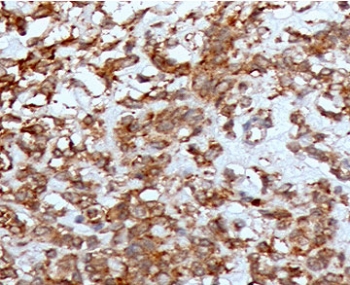

Cathepsin K Tissue Remodeling Protease Antibody Liver Tissue IHC. Immunohistochemistry analysis of FFPE human liver tissue using CTSK Antibody (clone CTO2-1) shows diffuse granular cytoplasmic staining in scattered cell populations, consistent with CTSK / Cathepsin K localization in lysosomal compartments associated with matrix remodeling activity. The punctate staining pattern reflects protease involvement in extracellular matrix turnover, while hepatocytes display comparatively lower background staining. Hematoxylin counterstain provides nuclear contrast and structural context. HIER: boil FFPE tissue sections in pH 9 10 mM Tris with 1 mM EDTA for 10-20 min and allow to cool before testing.

This CTSK Antibody / Cathepsin K Tissue Remodeling Protease Antibody is uniquely positioned for studies examining structural remodeling of tissues rather than general lysosomal protease activity. In immunohistochemistry, CTSK is typically observed as granular cytoplasmic staining in osteoclasts and other matrix-remodeling cells, as well as in tumor-associated stromal populations. This staining pattern reflects lysosomal localization coupled with active participation in matrix degradation processes. Detection of CTSK provides insight into areas of active tissue turnover, fibrosis, or invasive growth.